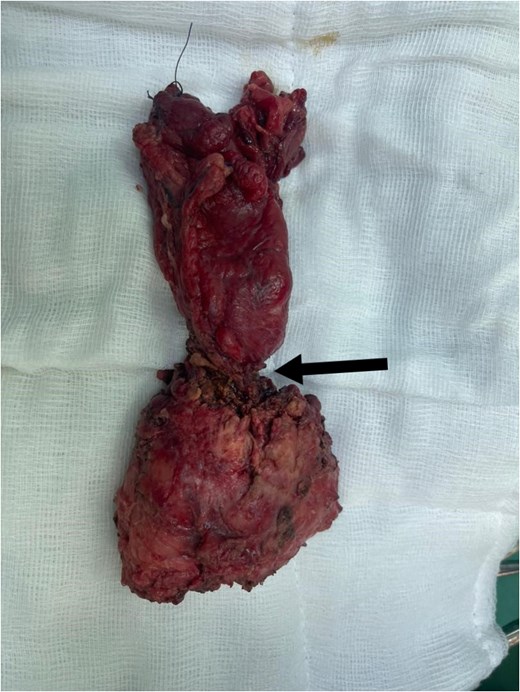

Three months later, he presented with lower abdominal pain and a rapidly enlarging umbilical swelling (Sister Mary Joseph’s nodule) (Fig. 4). A CT scan confirmed tumor recurrence and peritoneal carcinomatosis. Colonoscopy also indicated recurrent disease, and the patient was planned for adjuvant chemotherapy.

Red arrow: Sister Mary Joseph nodule. Black arrow: Wound dehiscence at the lower edge of the midline incision.